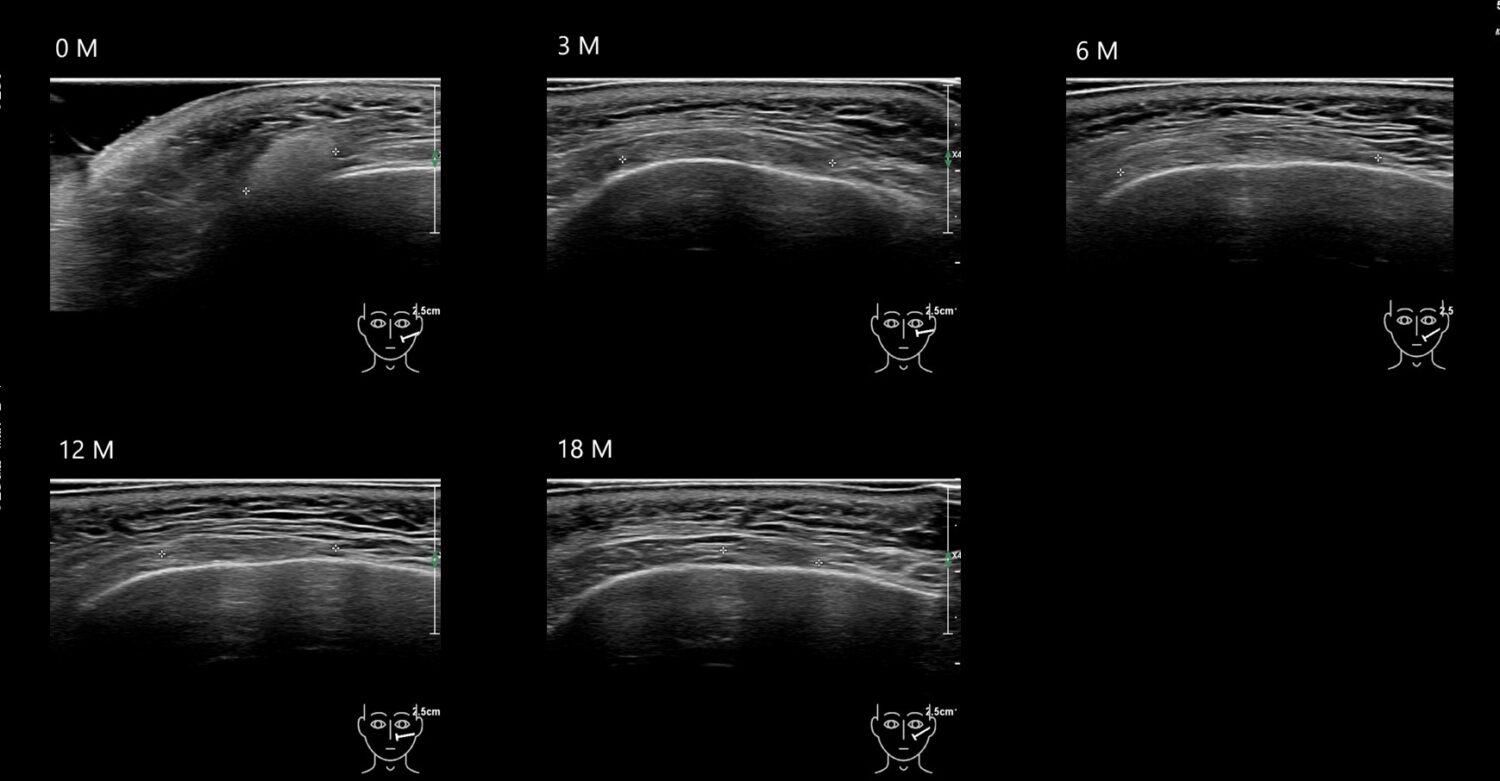

Draw in the image on the right where the fillers are located. To check if your answer is correct, please click on the secondary image.

Draw in the second image below where the fillers are located. To check if your answer is correct, swipe the first image to the right.